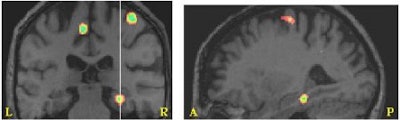

Reaction times on a word-meaning judgment task decreased with increased regional cerebral blood flow to the right parahippocampal gyrus (below) and the left hippocampus (above). Images courtesy of Christine Whatmough, Ph.D.